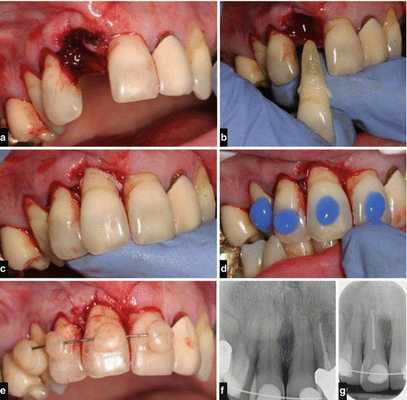

Лечение неполного вывиха

Если у пациента наблюдается неполный вывих, то лечение начинают с проводникового обезболивания, после чего врач аккуратно репонирует (устанавливает в лунку) зуб. Репозиция проведена правильно, если при смыкании челюстей отсутствует соприкосновение травмированного зуба с антагонистом.

После проведённых лечебных мероприятий вывихнутый зуб иммобилизируют (обездвиживают). Для этого врач использует индивидуальную шину-каппу, изготовленную непосредственно на пациенте. В шину обязательно включают не менее двух здоровых зубов по обе стороны от неполного вывиха. Шину накладывают минимум на 5-6 недель.

Перед шинированием и в динамике лечения проверяют электровозбудимость (реакцию на электрический ток) сосудисто-нервного пучка. Понижение или отсутствие электровозбудимости не только в первые 1-2 недели после травмы не обязательно говорит о необратимых изменениях. Реакция пульпы может приходить в норму в течение нескольких месяцев. Но если обнаруживаются клинические признаки гибели пульпы, её необходимо удалить, а канал пролечить, иначе оставшаяся в канале мёртвая пульпа приводит к развитию острого периодонтита или периостита.

Лечение полного вывиха

В случае полного вывиха зуба, если с момента травмы прошло не более двух суток, проводится его реплантация (установка зуба обратно в лунку) [8] .

Реплантацию проводят по общепринятой методике:

- Травмированный зуб промывают и помещают в изотонический раствор натрия хлорида с антибиотиками до самой операции.

- Если после вывиха прошло не более 10 часов, можно реплантировать зуб, не проводя эндодонтическое лечение (лечение корневых каналов). В таком случае эндодонтическое лечение зуба проводят через 2-3 недели после реплантации, когда становится очевидным приживление зуба.

- Если с момента вывиха прошло более 10 часов, пульпу полностью удаляют, а канал после механической и медикаментозной обработки пломбируют. Зуб после реплантации выводят из прикуса и укрепляют путём шинирования с помощью пластмассовой шины-каппы. Снимают её только через 3-4 недели.

- После реплантации необходимо в течение от одного до двенадцати месяцев проводить рентгенологический контроль. Это позволяет судить о состоянии корня зуба, периодонта и кости.